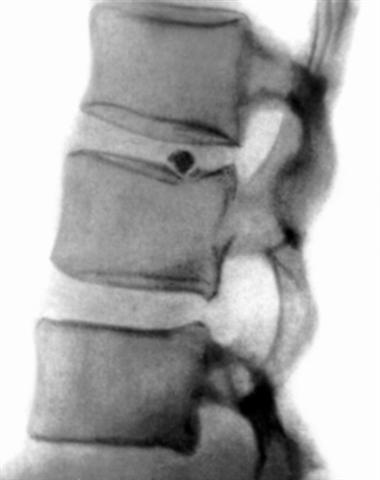

Рис. 7б). Рентгенограмма позвоночника (боковая проекция) при кальцификации межпозвоночных дисков: кальцификация части грыжи межпозвоночного диска; кальцификаты указаны стрелками.